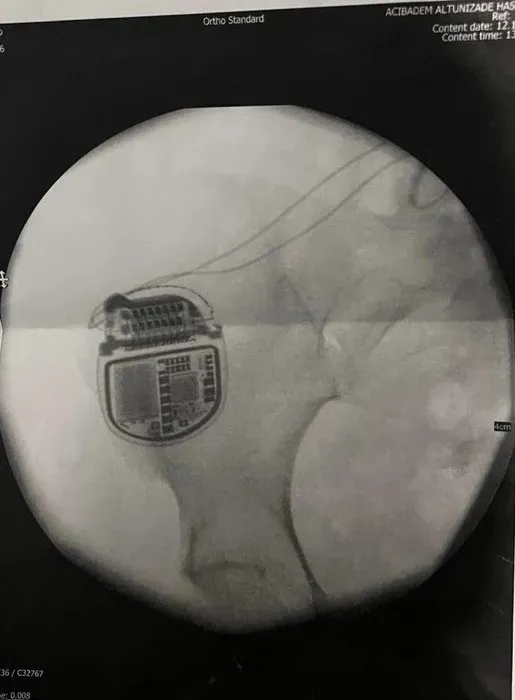

Eyüpsultan'da 1 Mart 2024 tarihinde Doktor Bülent Cihantimur'un 17 yaşındaki oğlu ehliyetsiz bir şekilde araç kullanarak bir kişinin ölümüne neden olmuştu. Yaşanan olay sıcaklığını korurken Bülent Cihantimur'a kalça büyütme ameliyatı olup ardından felç kaldığını iddia eden kadın yaşadığı mağduriyeti anlattı. 27 yaşındaki Z.T., "Ömür boyu pillere mahkum kaldım" ifadelerini kullandı. İşte detaylar...

Deri altına koyulması gereken silikon kas altına koyulduğu için iki bacağımda da ağır siyatik hasarından kaynaklı felç geçirdim. 15 gün Cihantimur'un hastanesinde yattım. Daha sonra benim kalçamdaki silikonu çıkardılar. Çünkü hastane raporlarında silikonları takmaya devam edersem hayatımın sonuna kadar felçli bir şekilde hayatıma devam edecektim. Silikonu çıkardıktan sonra beni hastaneden attılar. Hastanede yattığım sürede hukuka aykırı bir şekilde ben ilaçların ve narkozun etkisindeyken evrak imzalattılar. Bu evrak Bülent Cihantimur'dan şikayetçi olmamam, onun adını hiçbir yerde geçirmeyeceğime dair ve hiçbir mahkemeye başvurmamam içinmiş" dedi.